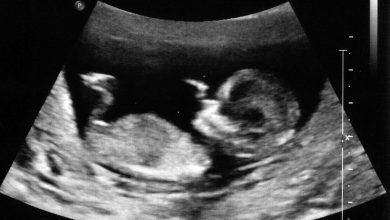

Диагностика зертханалық анализдер (қан, зәр), УДЗ және КТ көмегімен жүргізіледі.